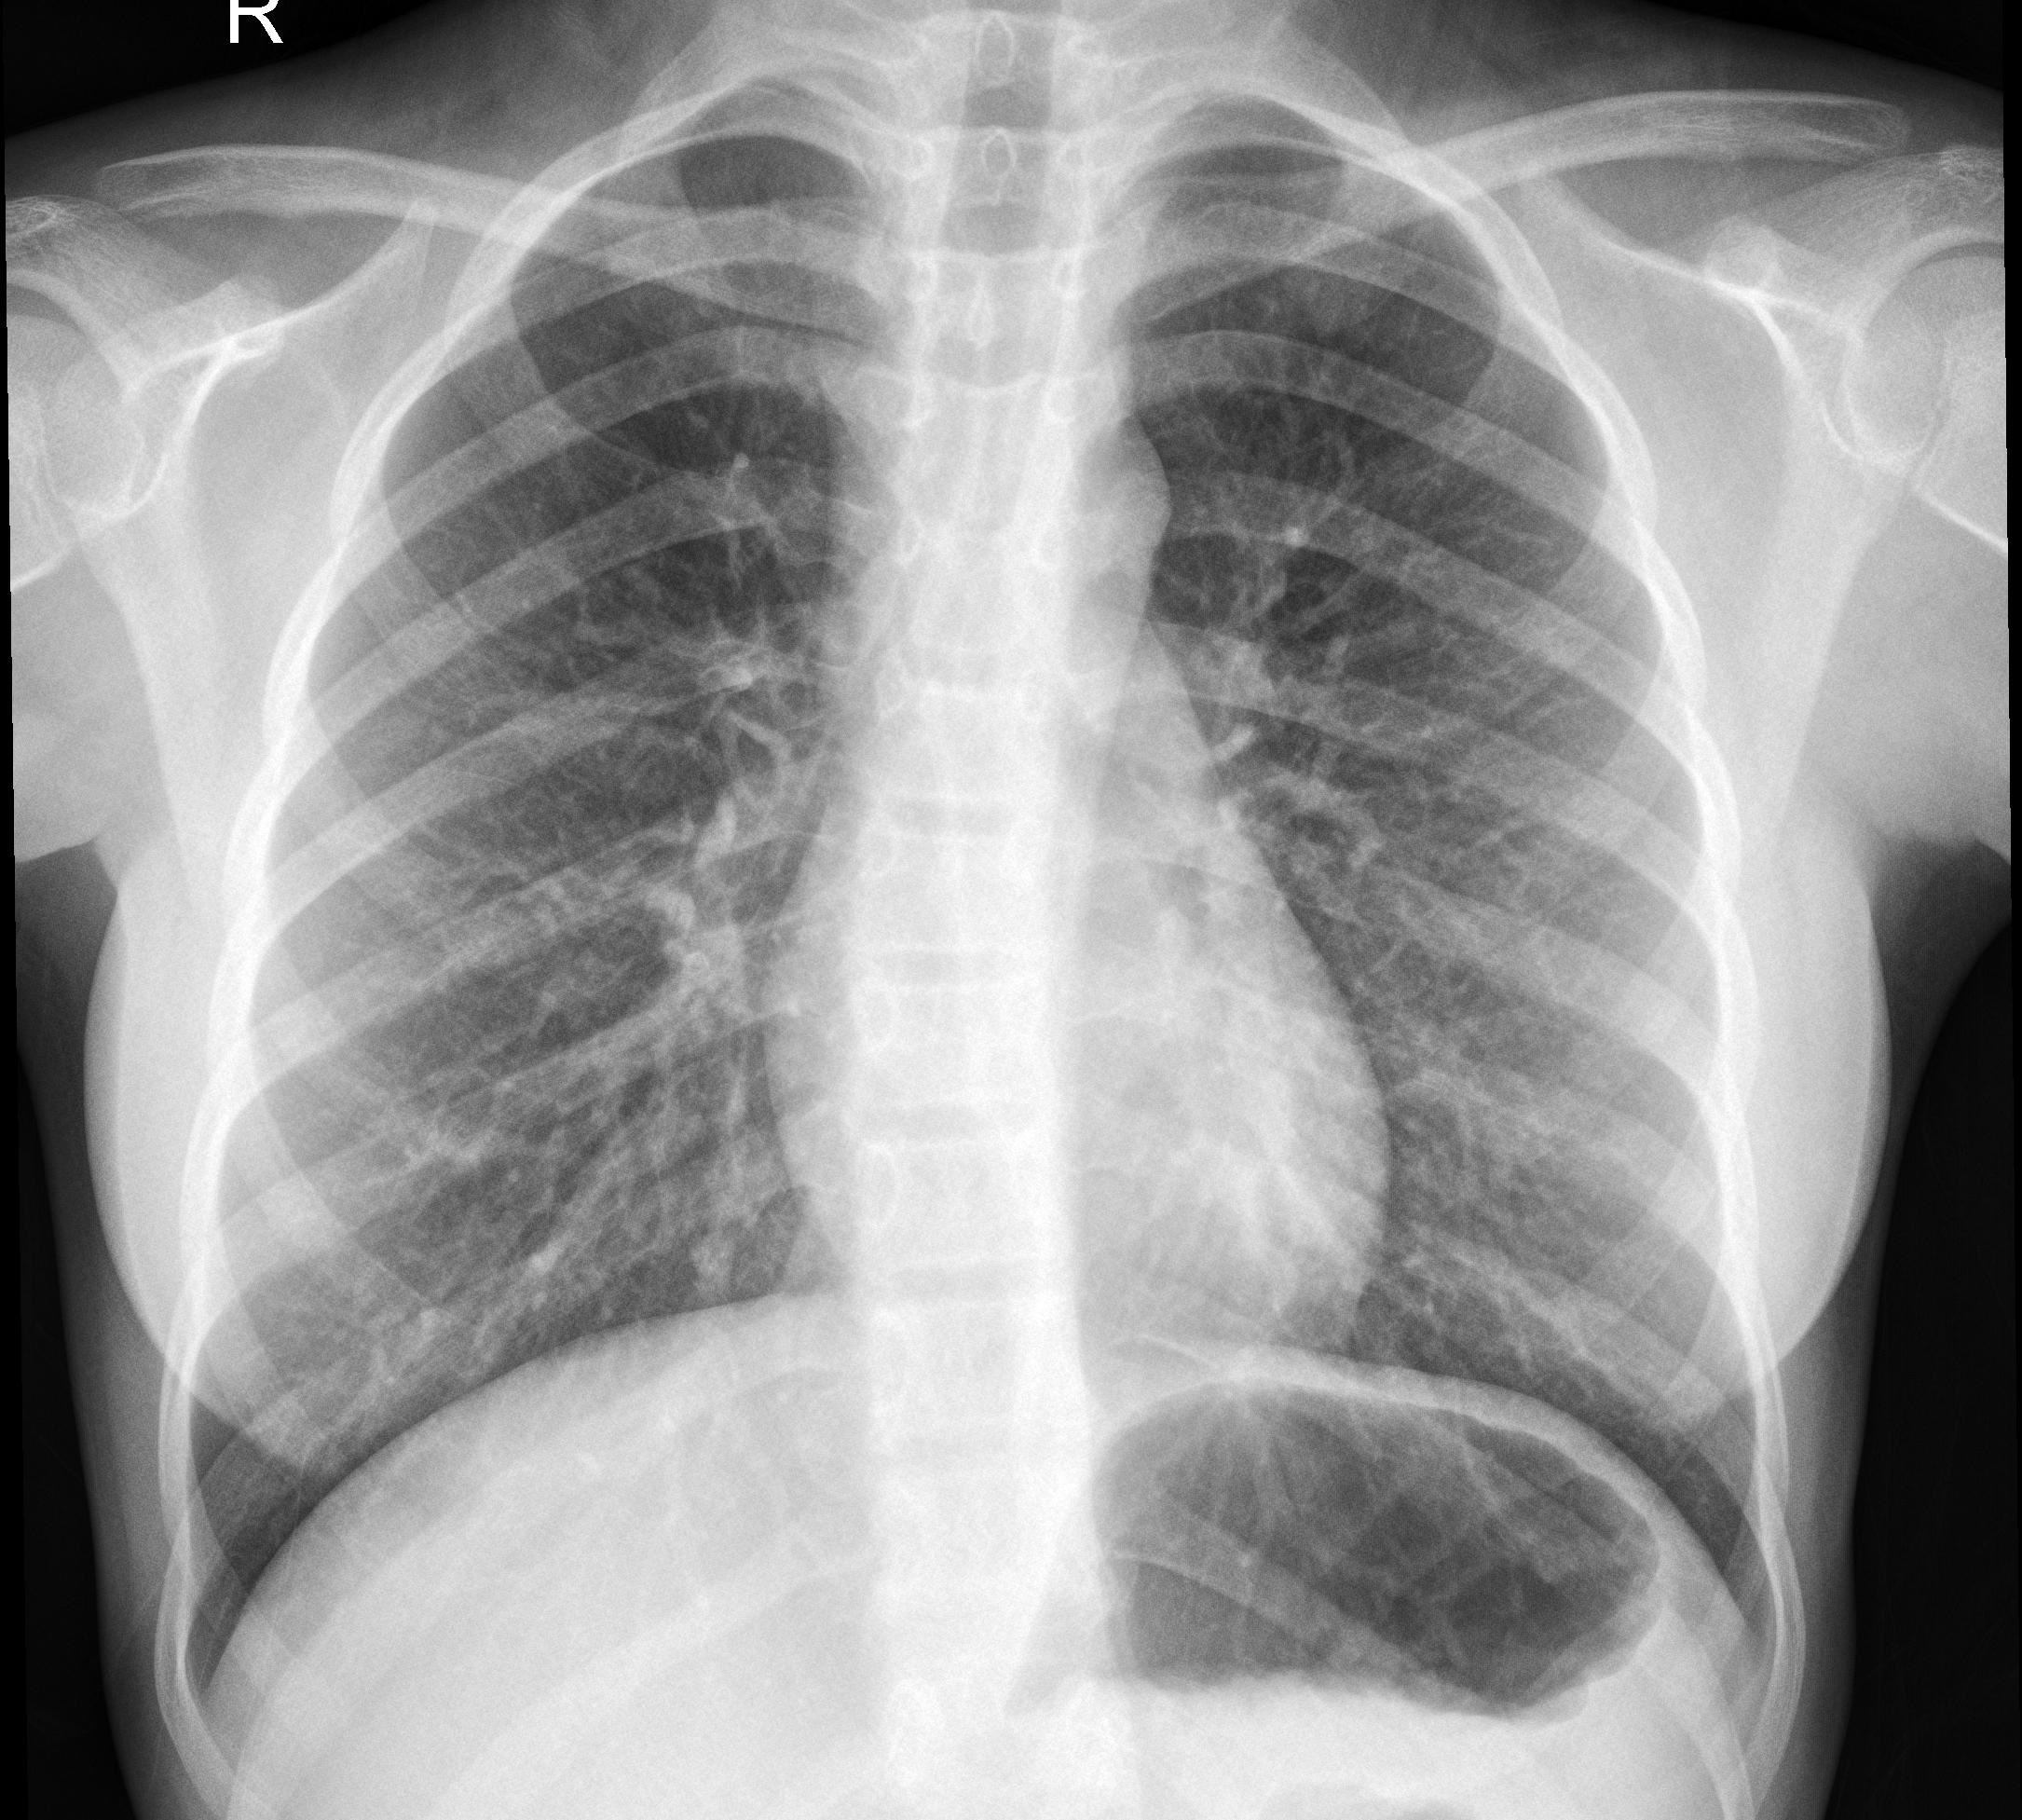

نمونه تصاویر افراد مبتلا به کرونا

نمونه تصاویر افراد فاقد کرونا

بازه زماني بين عكسبرداري تا تشخيص در حدود پنج تا ده روز به طول ميانجامد. خطاهاي تصويربرداري، تشخيص راديولوژيست و خطاي پزشك از جمله موانع موجود در تشخيص صحيح ميباشند. با وجود سيستم تشخيصگر مبتني بر هوش مصنوعي، ميتوان اين بازه زماني را كاهش داده و خطاي تشخيصي را كمتر كرد.